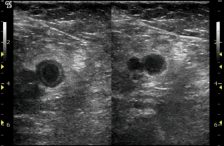

Patients may have other symptoms as well. For instance, because most pulmonary embolism start as a deep vein thrombosis, a patient may focus on leg symptoms such as a swollen leg.